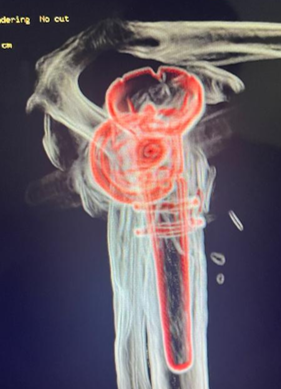

Procedimento Cirúrgico

Data da cirurgia: 12/07/2022

Implantes utilizados:

Base plate small

Glenosfera 36

Corpo proximal com haleta

Abordagem técnica:

Cimentação e lateralização foram consideradas para garantir melhor estabilidade

Redução anatômica das tuberosidades